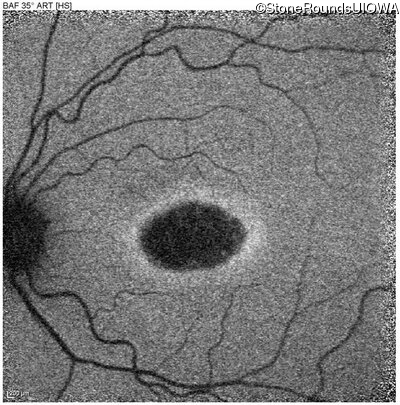

Blue Autofluorescence - Right - 20/32 sc

Exemplar